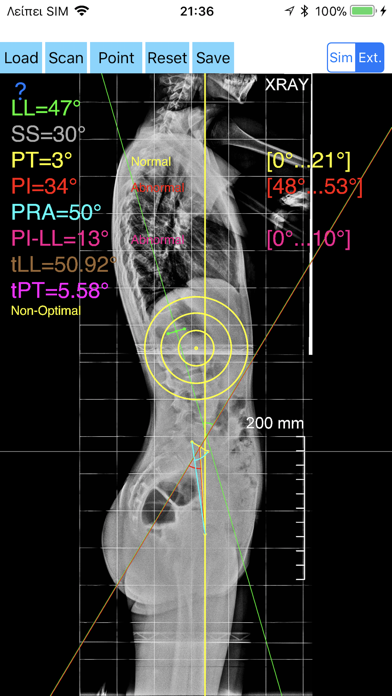

1. -By marking few points at the image of X-ray, the App calculates and offers a very convenient way to determine the most accurate possibly way at once, Pelvic incidence (PI), Sacral slope (SS), Pelvic Tilt (PT), Lumbar lordosis (LL), thoracic kyphosis, PI–LL Pelvic incidence Angle (PI) minus Lumbar lordosis Angle (LL) PI–LL, theoretical normal pelvic tilt (tPT),theoretical normal L1-S1 lumbar lordosis (tL1S1), Pelvic Radius Angle (PRA).

2. Radiographic parameters to evaluate objectively the spinopelvic sagittal balance are Pelvic incidence (PI), Sacral slope (SS), Pelvic Tilt (PT), Lumbar lordosis (LL).

3. -The app offers theoretical value estimation this is particularly useful because a sensible difference between theoretical value and measured value reveals a compensation phenomenon if the pelvis tilt (PT) is higher than its theoretical value, then it is due to pelvis retroversion, which is a compensation phenomenon.

4. Knowing the theoretical value of Pelvis Tilt (PT) provided it is easy to understand that a sensible difference between theoretical value and measured value is a compensation phenomenon.

5. Drawings in patients X-rays and precise measurements are important in order to quantify the magnitude of spinal deformities, to monitor the success or failure of treatment and thus optimise the management of patients according to the severity of the imbalance or even to identify patient at risk of degenerative spondylolisthesis or disk herniation.

7. -Save the planned images, for later review or consultation.The measured values are compared by normal reference databases and also data are exported as txt file, ready to print or to input as cells to excel for research.

8. The app offers a very convenient and accurate way to perform most common radiographic measurements for spine, at the spinopelvic juncture in a blink of an eye in front of your screen.

10. -The app allows choosing between simple and extended method according to everyday preference and also by choosing points in vertebra body in a independent manner from order.

11. According to measured parameters the app categorises the severity of the imbalance of spine, in different stages: optimal or non optimal.